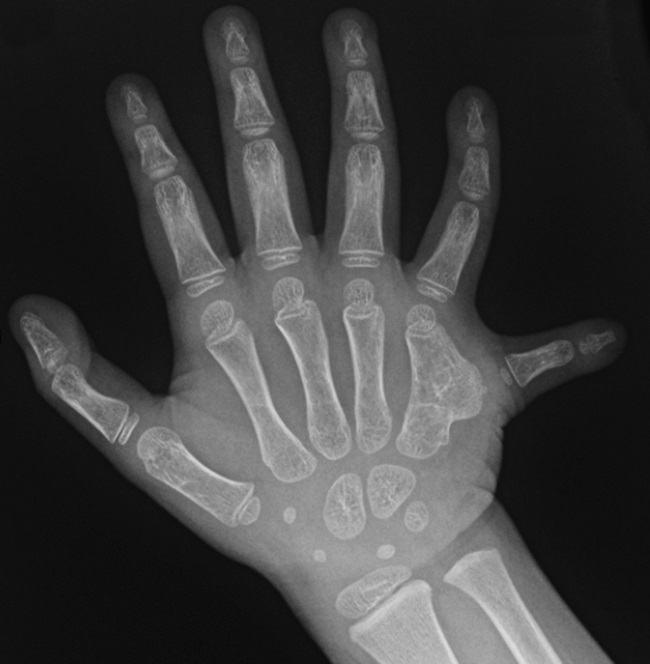

polydactyly

Polydactyly, with an extra little finger.

Reproduced from Comer GC, Potter M, Ladd A. Polydactyly of the Hand. J Am Acad Orthop Surg 2018. 26(3):75-82.

Polydactyly is the presence of one or more extra fingers on the hand. An extra finger may be:

• Small and nonfunctional — made of only skin and soft tissue

• Fully formed with bones of its own

Most commonly, an extra finger is to the right of the thumb or the left of the little finger (when the palm is facing down). Rarely, an extra finger is between the other fingers.

Polydactyly often runs in families and is sometimes associated with other medical conditions or syndromes. In some cases, babies born with polydactyly will have syndactyly as well.